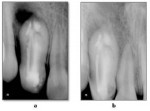

A 13-year-old female was referred to the Department of Pedodontics and Preventive Dentistry at Rural Dental College and Hospital in Loni, India, with a chief complaint of past swelling in the upper right front of the jaw. The patient described diffuse swelling in the right front of the cheek, which had resulted in elevation of the ala of her nose. On intraoral examination, a deep pit was observed in the permanent maxillary right lateral incisor with slight discoloration of the crown, and the tooth responded positively to vertical percussion. Examination of a preoperative radiograph showed the presence of dens invaginatus of the maxillary right lateral incisor with an apical radiolucent area (Figure 1A). A diagnosis of type III (Oehlers) dens invaginatus with dentoalveolar abscess was made. The patient had a noncontributory medical history.

At the 1-week follow-up visit for suture removal, the tissues were noted to be healing uneventfully. At 1.5 months post-treatment, the patient had no symptoms. Signs of hard-tissue healing in the periradicular area could be appreciated on the radiographic examination (Figure 2B). Follow-up radiographic scans taken 6 months later showed evidence of complete healing.